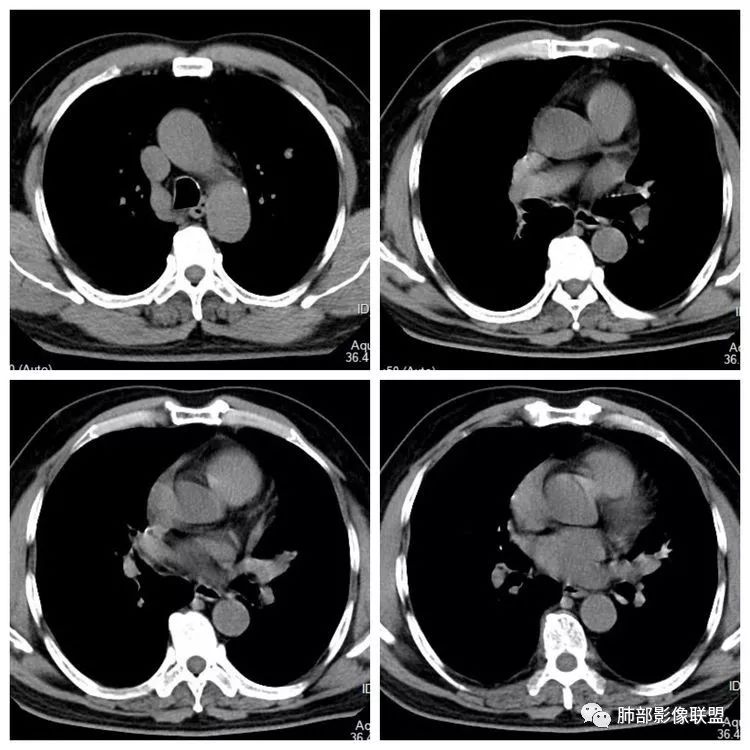

患者,男 ,66岁, “左肺占位”收住院。CEA 5.23 轻度增高 医学百科网 | YxBaike.Com

平扫 动脉期 静脉期 40HU、48HU、57HU

左下叶内前基底段实性占位堵塞支气管,强化较弱,考虑肺癌可能 ,小细胞?腺癌?

肺内其他小结节,需怀疑转移可能 医学百科网 | YxBaike.Com

患者老年男性,“左肺占位”收入住院。查CEA轻度升高。胸部CT:左肺肺门占位并左肺下叶阻塞性,远端肺组织膨胀不全,增强可见轻度强化,内似见低密度灶。双肺多发类圆形结节,以左肺上叶尖后段为大,内可见部分钙化,边缘光滑、清楚。综合考虑恶性病变,鳞癌并转移可能大,鉴别腺癌、结核。

胸CT:左下叶内前基底段肿块,支气管堵塞,强化弱,延迟强化,两肺多处结节,右上肺门淋巴结大。常规考虑:肺癌可能 ,肺内小结节,转移?鉴别:错构瘤,TB等。 医学百科网 | YxBaike.Com

左肺下叶占位,左肺下叶前内支气管阻塞可疑(缺乏薄层),病灶有膨胀性,远端较内侧细,增强病灶强化不明显——乏血供病灶,病灶沿支气管生长,考虑恶性病变,左肺上叶可见小结节病灶,边缘光滑清晰,考虑转移瘤,综上所述考虑恶性病变,左肺下叶小细胞类癌可能,左肺上叶转移。

下面这个图可以看到病灶整体有彭隆以及强化不均

1.定位:左肺块影同时累及下舌段及下叶内基底段且相互延续。病灶跨叶,或存在叶裂发育异常,或者说就是病灶的肺门蔓延。 医学百科网 | YxBaike.Com

2.病灶前上部分与舌段支气管相关且形成阻塞。

3.左肺上叶另见孤立结节影,边界清楚光整,中央钙化,未见脂质密度特征。 医学百科网 | YxBaike.Com

4.增强扫描左肺门区块影轻度强化,强化程度轻于舌段周围不张肺组织。

左肺上叶孤立小结节影未见异常强化。 医学百科网 | YxBaike.Com

5.双肺门及纵隔未见明确增大淋巴结。

6.分析:男性患者,左肺门区块状影,支气管阻塞,强化不显著,未见淋巴结肿大,更多见于肺鳞癌。难以解释的是下肺病灶的生长方式。 医学百科网 | YxBaike.Com

沿肺门或是叶裂缺损孤立发生且蔓延,转移性腺癌似乎可以解释,但占据较大支气管腔就属罕见了。 医学百科网 | YxBaike.Com